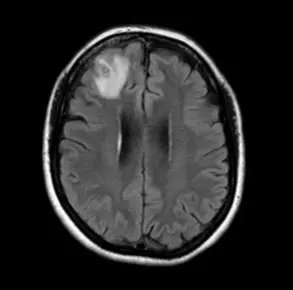

18일(현지시간) 뉴욕포스트 보도에 따르면 3주간 태국, 일본, 하와이 여행을 다녀온 여성 A 씨(30)씨가 뇌와 척수에 염증을 일으키는 기생충 감염병 ‘광동주혈선충증(angiostrongyliasis)’에 걸렸다.

A 씨의 진단명은 광동주혈선충증이었다. ‘쥐 폐선충’으로도 알려진 이 감염병은 광동주혈선충의 중간숙주(조개 등의 담수산 패류와 민달팽이)나 운반숙주(새우, 게, 개구리 등)를 덜 익혀 먹을 경우 감염된다. 때로는 유충으로 오염된 채소를 섭취하거나 물을 마시는 경우에도 감염될 수 있다.

쥐 폐선충의 초기 증상은 구역, 구토, 복통 등이며 두통, 발열, 근육 통증, 피로, 불면증 및 신경학적 증상이 나타날 수 있다. 목 경직과 통증, 피부의 따끔거림이나 타는 느낌, 복시, 배뇨 또는 배변 어려움, 발작 등이 동반될 수 있다. 어린이의 경우 발열, 무기력, 위장 통증, 근육 경련, 경련 및 사지 약화 등의 증상이 나타날 수 있어 주의해야 한다.